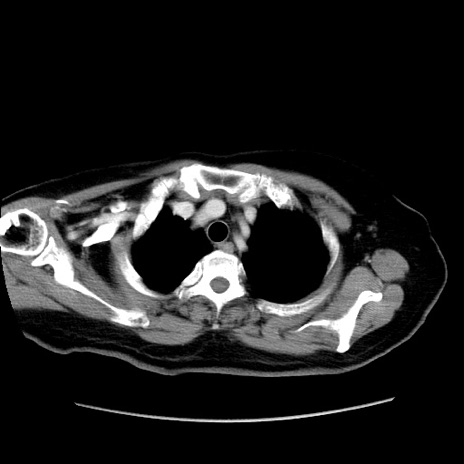

症例19(横断像)

【症例】80歳代女性

【主訴】下腹部痛

【現病歴】約8時間前より下腹部痛の出現あり、救急外来受診。

【既往歴】両側付属器切除

【身体所見】意識清明、下腹部正中に手術痕あり、その部位に一致して圧痛と反跳痛あり。腸蠕動音は亢進。

【データ】WBC 9300、CRP 0.15